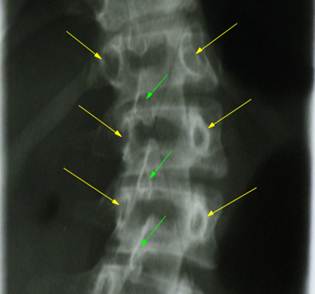

Слева

фрагмент прямой рентгенограммы позвоночика со сколиотической деформацией. Видны

верхние края латеральных масс крестца, лежащие на одном уровне относительно

горизонтали снимка. Вероятно, что

деформация позвоночника не связана с наклоном таза. Справа представлен аналогичный фрагмент, но

верхние края латеральных масс крестца лежат на разных уровнях – это признаки

наклона таза вправо. Возможно, что деформация позвоночника связана с

укорочением правой ноги и боковым наклоном таза. Зеленые стрелки обозначают верхние края латеральных масс.